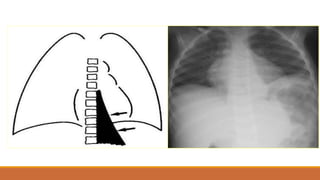

PHIM THẲNG ĐỨNG

•TÙ GÓC SƯỜN HOÀNH

•BÓNG MỜ VÙNG THẤP XÓA BỜ VÒM HOÀNH VỚI

GIỚI HẠN TRÊN LÀ ĐƯỜNG CONG DAMOISEAU

•ĐẨY TRUNG THẤT VỀ PHÍA ĐỐIDIỆN

•XẸP PHỔI THỤ ĐỘNG (+/-)

•THAY ĐỔI THEO TƯ THẾ

TDMP lượng ít